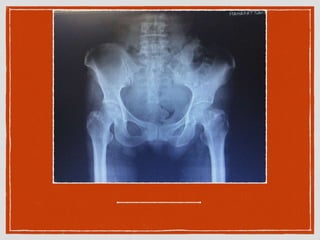

pelvis AP, Chest x-ray

Diagnosis + management Severehead injury (high risk) r/o base of skull fracture Refer จากรพ.ด่านขุนทด consult neuro surgery CT brain non contrast pelvis AP, Chest x-ray